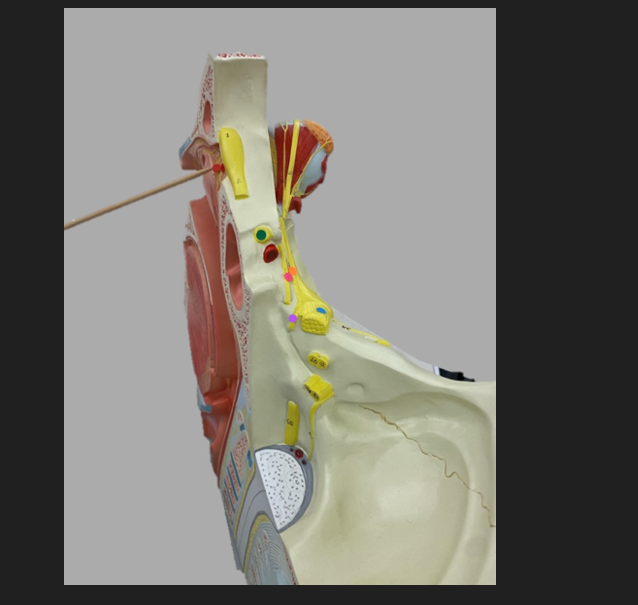

green dot

spinal nerve

orange dot

ventral root

pink dot

dorsal root

blue dot

dorsal root ganglion

red dot

dorsal ramus

yellow dot

ventral ramus

purple dot

anterior median fissure

red dot

posterior (dorsal) horn

purple dot

lateral horn

dark blue dot

anterior (ventral) horn

orange dot

dorsal column

yellow dot

lateral column

dark green

anterior column

line green and pink doit

gray commissure

light blue dot

posterior median sulcus